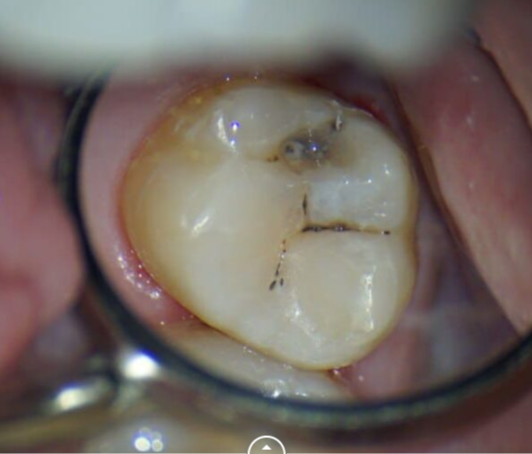

Сокольская Оксана Юрьевна: портфолио (2)